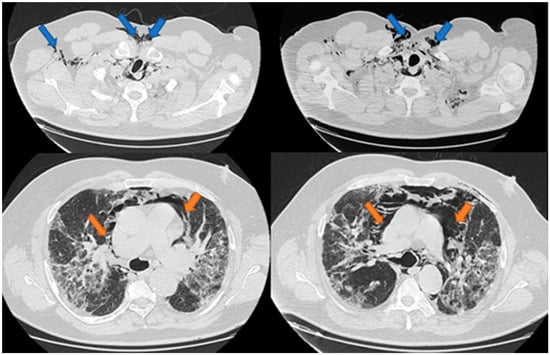

Spontaneous Pneumomediastinum, Pneumothorax, Pneumopericardium and Subcutaneous Emphysema—Not So Uncommon Complications in Patients with COVID-19 Pulmonary Infection—A Series of Cases